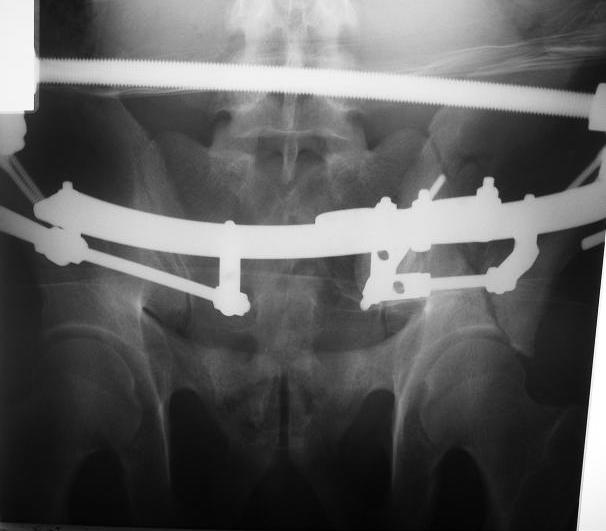

Поступил пациент после кататравмы (упал с высоты 4м). После обследования установлен Ds: Сочетанная травма. ЗТГК перелом 5-6 ребер справа. Ушиб левого леогкого. Оскольчатый перелом крыла подвздошной кости слева, со смещением. в экстренном порядке выполнена операция о/синтез таза стержневым аппаратом. Снимки прилагаются. Пациент со 2-го дня стал ходить без костылей. Из анамнеза жизни у пациента имеется гепатит В и С, с 1998г. употребляет наркотики (героин 1г в день нормальная доза). На контрольных снимках таза в аппарате смещение отломков сохраняется, да еще и стержни сломались. Подскажите ув.коллеги, как поступить в данной ситуации: оставить все как есть или добиваться репозиции в аппарате, или планировать на открытую репозицию. На сегодняшний день пациент стабилен, по анализам компенсирован. Принимает героин по другому справиться не может. С ув. Андрей

А сколько времени прошло после травмы? Аппарат лучше убрать: в таком виде он не выполняет никаких функций, а сломанные стержни скорее всего воспалятся и помешают доступу, если решите оперировать открыто. Целесообразно, как мне кажется сделать проекции Judet, чтоб определиться с линией перелома и возможным вовлечением вертлужной впадины. Вообще же лечение переломов крыла аппаратом - дело достаточно утомительное и часто неблагодарное - сложно управлять ротационным смещением и отведением/приведением фрагментов крыла, можно ухудшить стояние отломков.

C момента травмы прошло ровно 10 дней. Да Максим, вы как в воду глядели, у стержней появились признаки воспаления. Аппарат демонтирую.